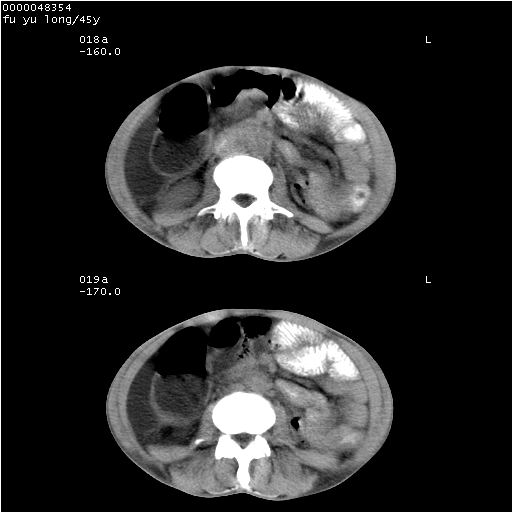

以下是引用医影拾贝在2008-5-30 2:38:00的发言:[br]气肿性胃炎、胃十二指肠溃疡、腹膜炎,考虑穿孔可能性较大

以下是引用lkc8963在2008-5-30 8:44:00的发言:[br]胃窦癌伴网膜(胃结肠韧带)/腹膜及腹膜后淋巴结转移.